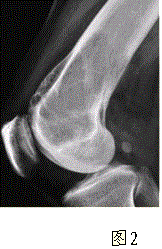

问题 患者女,35岁,左膝关节隐痛1年余,近1周加重,活动后明显疼痛。查体:左股骨下端外侧肿胀,压痛。行左膝关节正侧位CR,并行左膝关节CT扫描,见下图。 依据此病变的CT表现,以下说法正确的是

选项 A.病变边缘清晰 B.CT示左股骨外髁骨皮质不完整,提示病变为恶性或生长活跃 C.病灶内部密度不均 D.病灶周围可见软组织肿胀,提示为炎性病变 E.病灶无明显硬化缘 F.病灶呈中心性生长

答案 ABCE

解析 ABCE